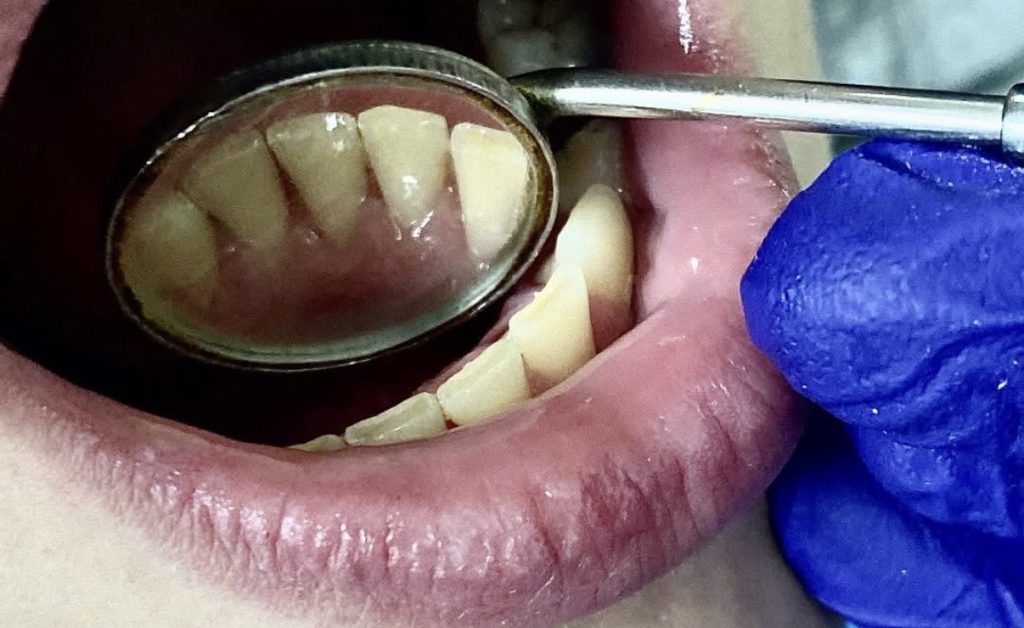

Slika 2: Stanje nakon profesionalnog uklanjanja kamenca

Profesionalno čišćenje zuba nije samo estetski tretman već važna stomatološka procedura. Za razliku od mekih naslaga koje se mogu ukloniti svakodnevnom oralnom higijenom, zubni kamenac se čvrsto veže za zubnu površinu i može se odstraniti isključivo profesionalnim stomatološkim tretmanom.

Njegovo prisustvo stvara hrapavu površinu pogodnu za daljnje nakupljanje bakterija, što dovodi do upale gingive, pojave krvarenja desni i razvoja gingivitisa. Ukoliko se ne ukloni na vrijeme, upalni proces može napredovati u parodontitis – hronično oboljenje koje uzrokuje razaranje potpornog aparata zuba i predstavlja jedan od vodećih uzroka gubitka zuba kod odraslih osoba.